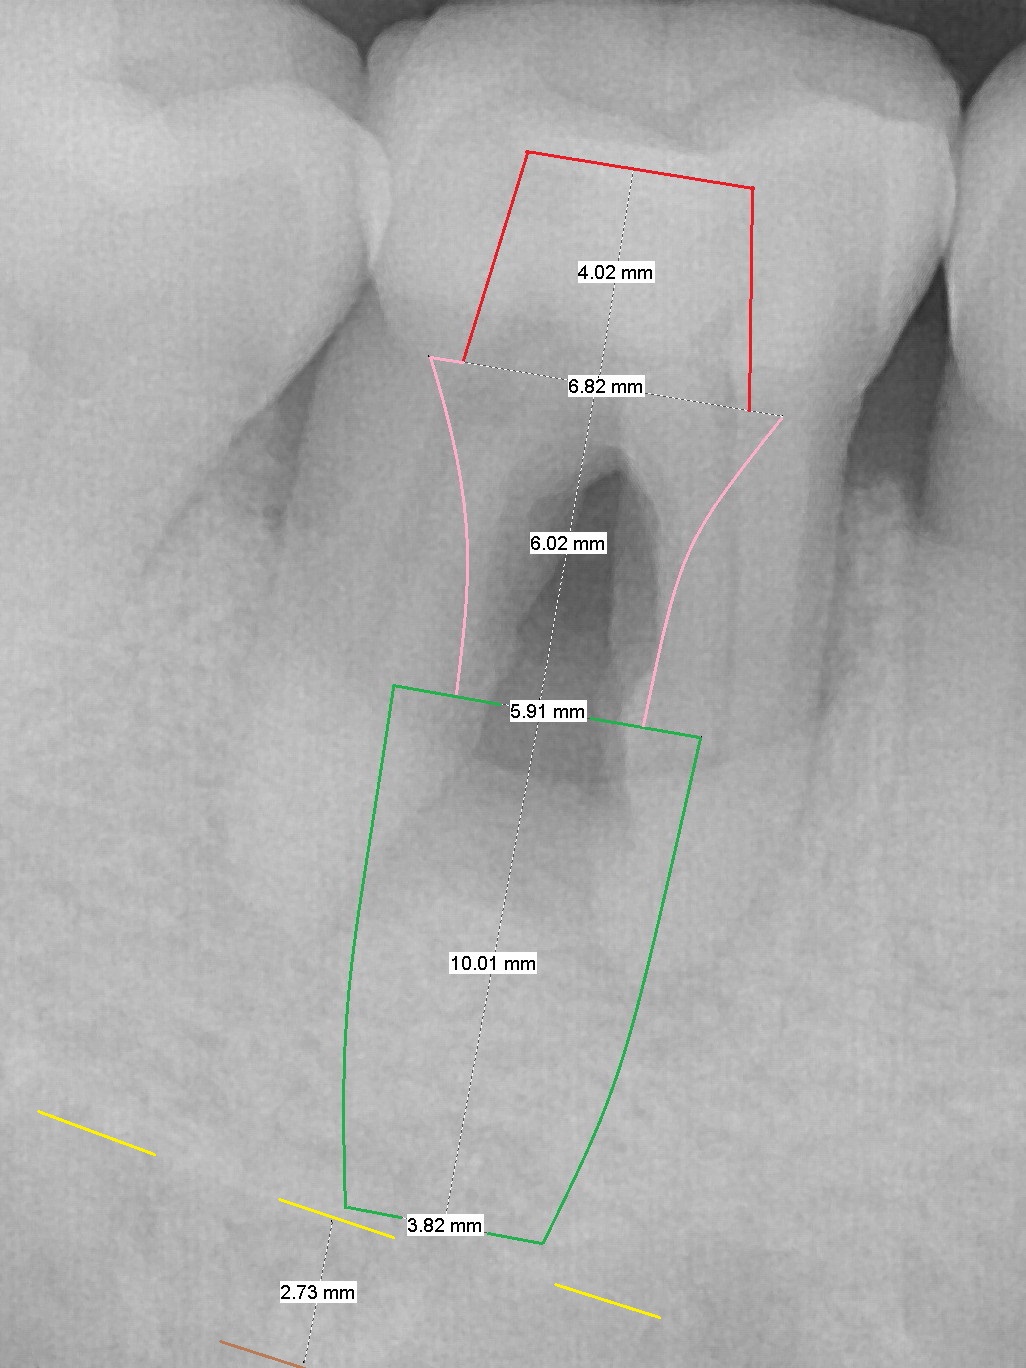

A 45-year-old man had Class I or II furcation involvement at the tooth #30 ten years ago (Fig.1, Classifications of Furcation Involvement - Stedman's Online). He returns recently requesting composite to seal Class IV furcation involvement (Fig.2). It appears that the tooth is unsalvageable (Fig.3 (no Antibiotic)). Since it is difficult to differentiate the upper (yellow dashed line) vs. the lower (brown line) borders of the Inferior Alveolar Canal, the initial depth will be 8 mm. Take panoramic X-ray if necessary. Because of severe bone loss, an abutment with 6 mm cuff is to be used (Pink area).